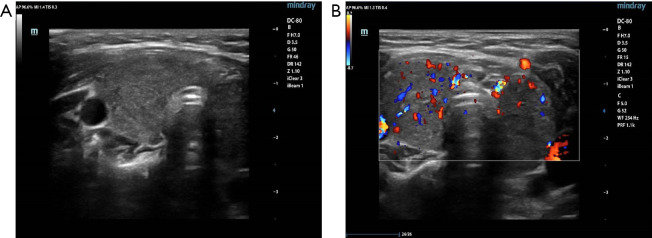

Case description: On the initial hospitalization, the patient presented with sudden onset of altered consciousness, tachycardia, and electrolyte disturbances, including hyperkalemia and metabolic acidosis. Following thyroid function tests and thyroid ultrasonography, a diagnosis of Graves' disease was made. Antithyroid treatment with methimazole and propranolol was administered, leading to an improvement in the blood gas and biochemical parameters. Although thyroid function was controlled, the patient's hyperkalemia, hyperchloremia, metabolic acidosis, and hypertension remained refractory to treatment. Further genetic testing revealed a KLHL3 gene mutation, confirming the diagnosis of PHA IID. After treatment with hydrochlorothiazide (10 mg), the patient's electrolyte imbalances and blood pressure normalized.